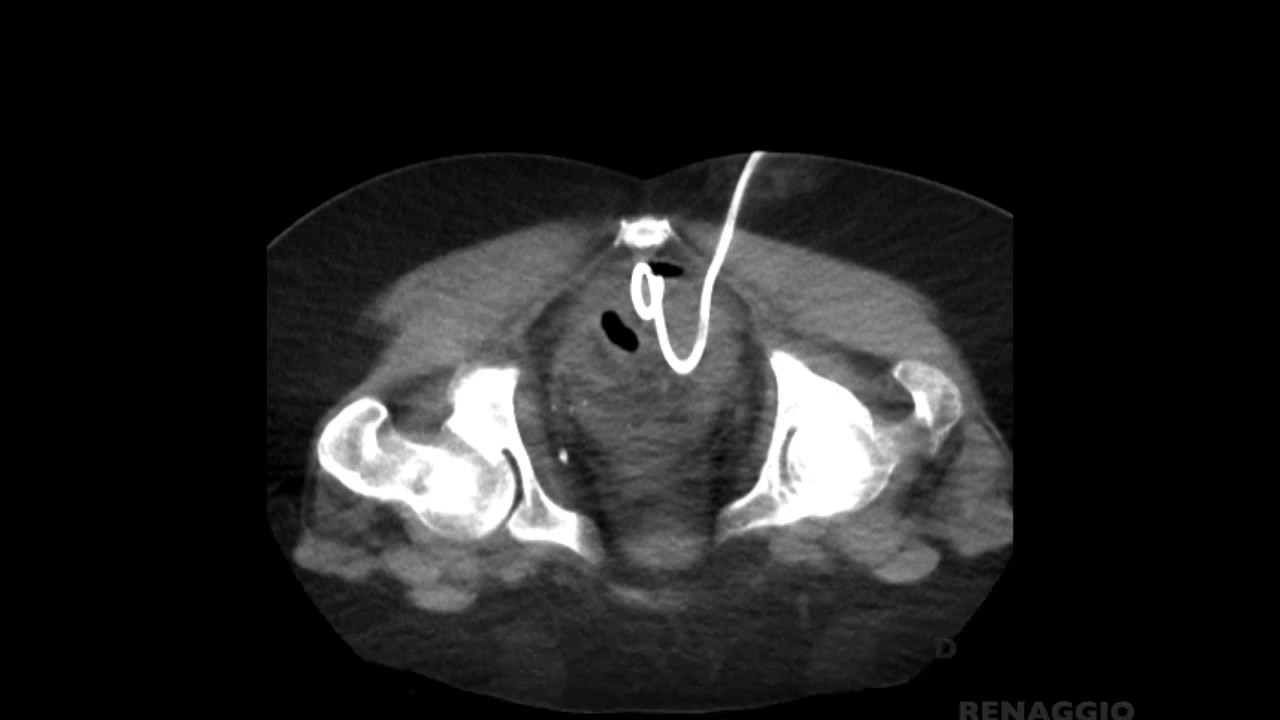

Percutaneous CTguided drainage of a pelvic collection YouTube Pelvic Fluid Collection Medical Term Pelvic fluid collections are classified into two categories: A fluid collection in the pelvis on ct can be free flowing or organized. Culdocentesis is a medical procedure that checks for abnormal fluid behind your vagina and under. Free flowing means that the fluid settles into the most. A fluid collection is a common finding in the pelvis on ct, especially. Pelvic Fluid Collection Medical Term.

ImageGuided Transvesicular Drainage of Pelvic Fluid Collections A Pelvic Fluid Collection Medical Term Free flowing means that the fluid settles into the most. A fluid collection in the pelvis on ct can be free flowing or organized. Pelvic fluid collections are classified into two categories: Culdocentesis is a medical procedure that checks for abnormal fluid behind your vagina and under. A fluid collection is a common finding in the pelvis on ct, especially. Pelvic Fluid Collection Medical Term.